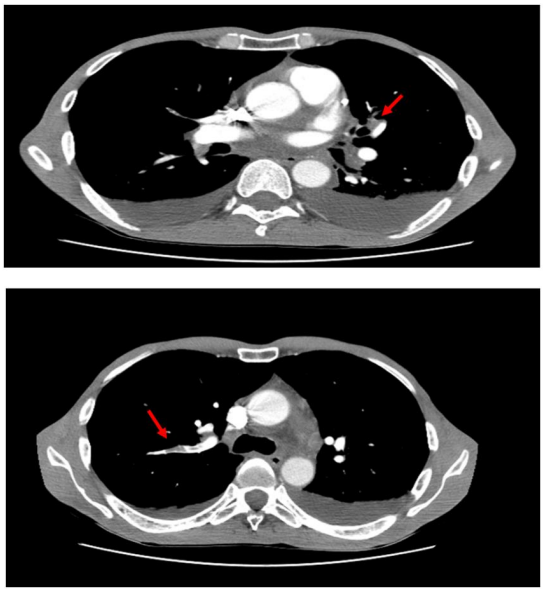

Angio Thoracic CT showing :(figure4)

- multisegmented pulmonary embolism (IO=40%), dilation of cardiac cavities + reflux cave: acute pulmonary heart;

- bilateral and pericardial pleural fluid effusion of moderate abundance;

Figure 4: chest CT angiography showing bilateral segmental and subsegmental pulmonary embolism and pleural effusion